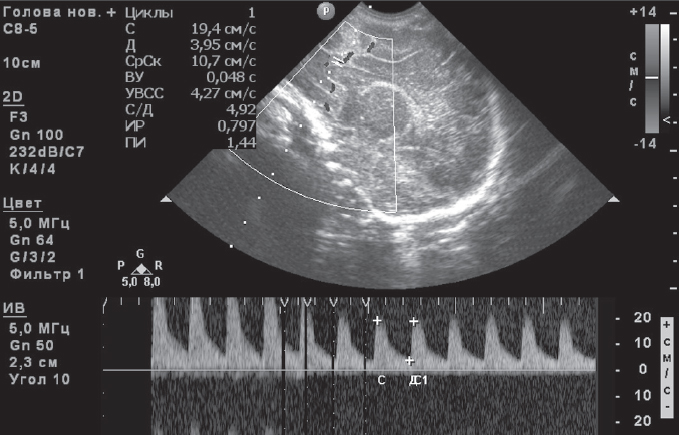

Clinical observation. This article presents the results of observing two women with premature amniotic fluid expulsion at 22 and 24 weeks’ gestation, respectively. In the first case, the woman was immediately admitted to the perinatal center; in the second observation, she was admitted after 3.5 weeks of treatment at another institution. In both cases, pregnant women had manifestations of oligo and endotoxemia, a protective inflammatory response in the mother-placental-fetal system (more pronounced in the second observation) against a background of urogenital infection. In the course of complex treatment, the patients underwent detoxification, of efferent therapy in the form of repeated consecutive sessions of plasmapheresis, hemosorption (one operation each), external photomodification of blood with ultraviolet, laser beams with prolongation of pregnancy by 10 and 8 weeks. The deliveries in both cases were operative with live babies with body weight of 1600 g and 1840 g, respectively. In the first case the infant did not need intensive care, was breastfed, in the second observation the newborn received active respiratory support for 9 days, in the dynamics his condition normalized. No septic complications in mothers and fetuses were observed.